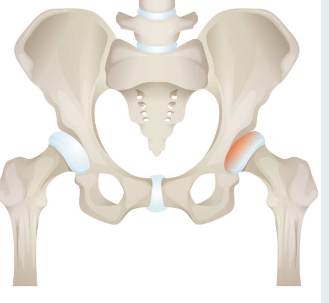

고관절 골절이란?

골다공증과 같은 뼈 약화 상태 또는 외상으로 인해 발생하는 대퇴골(허벅다리 뼈) 상단의 골절을 의미하는 것입니다. 일반적으로 낙상이나 직접적인 충격으로 인해 발생하며, 특히 고령자에서 흔히 일어날 수 있는 사고입니다. 고관절 골절치료는 주로 수술과 재활이 필요하며, 이는 환자의 이동과 삶의 질에 많은 영향을 미칠 수 있습니다.

고관절 골절 통증 증상

고관절 골절이 발생하면 큰 고통을 호소하며 움직이지 못한 경우가 가장 흔합니다.